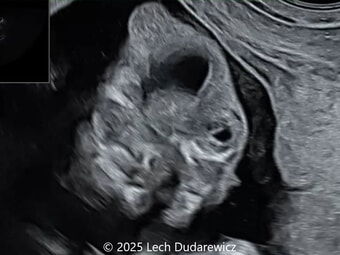

Case of the Week #638

A 36-year-old pregnant woman with non-contributory anamnesis was referred to our center at 12 weeks and 6 days of gestation following suspicion of fetal abnormalities on a routine first-trimester (11โ€“14 weeks) scan performed elsewhere.

Ultrasound findings are presented below.ย  What is the most likely diagnosis?